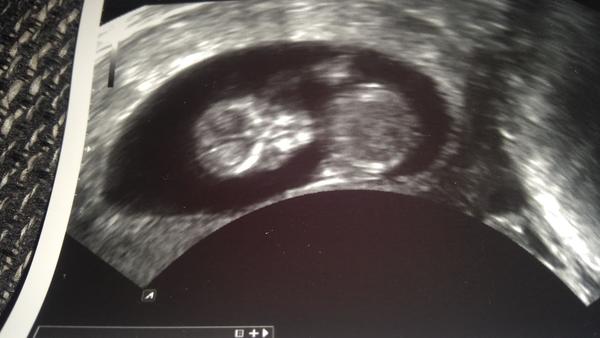

@tercasv ony ty cizí fotky na internetu jsou něco jiného, než když pak člověk vidí toho svého cvrčka 🙂 Mě tedy zase tak moc neoslovily přímo ty fotky - byť se nám povedly docela hezky, ale líbil se mi ten zážitek. Je vidět, jak se tam miminko tváří, jak zívá, dělá ksichtíky........🙂

Za mě fajn cesta do hlubin ...maminčina bříška - moc me bavilo, když jsem pak našla fotku ze 3D a fotku reálnou, které byly témeř totožné - tvář, výraz......

Musím říct, že to bylo super. Přesto, že nejsem zrovna hubená a mám placentu na přední straně, tak bylo mimčo krásně vidět. Oproti těm skoro mazaninám od gynekologa nesrovnatelné....

@tercasv Ja od toho moc neocekavala, premluvil me manzel, ze to zkusime, ze bychom treba litovali. Malej se nechtel ukazat oblicejem, takze jsme si dobre prohledli jeho zadek a naprosto presne vedeli, ze to bude kluk🙈 Pak se ale ukazal a stalo to za to. Mam fotku, kterou mam stale vytavenou na stole a rada se koukam, jak si byl po narozeni podobny, vcetne jeho mimiky😀 U me to tedy predcilo ocekavani, nejen ten vysledek, ale i ten zazitek byl fajn😀.

Stojí - ale až tak v tom cca 23-28 týdnu 🙂 to už je krásně vidět obličejík. Já mám od dcery i syna i moc pěkná videa 🙂